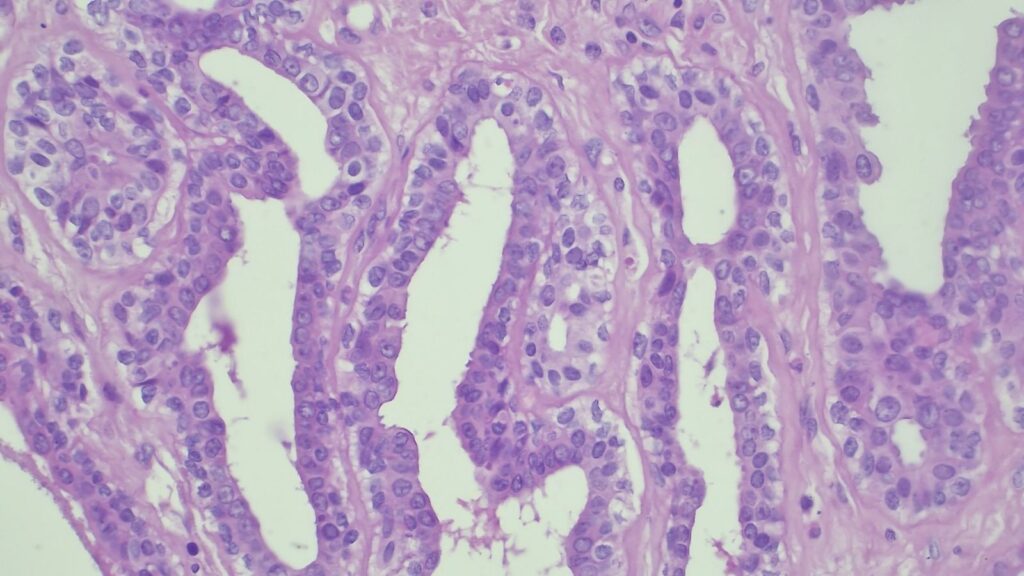

【病理形态学大解密:寻找良性证据】 仔细阅片后,专家指出了以下几个至关重要的形态学特征(见附带病理切片图):

✅ 腺体发育良好,呈圆形和分叶状结构。 ✅ 边缘虽略不规则,但整体呈推挤性(pushing)和局限性生长。 ✅ 无弥漫性浸润结构。 ✅ 无促结缔组织增生性间质反应(No desmoplastic stromal reaction,这是排除浸润癌的核心点)。 ✅ 细胞学形态温和(Bland cytology)。 ✅ 在慢性炎症和纤维化的背景下,仅见单个典型的核分裂象。 在病变外周,腺体表现出被瘢痕样间质压迫和塑形的特征,而不是破坏性或浸润性生长。